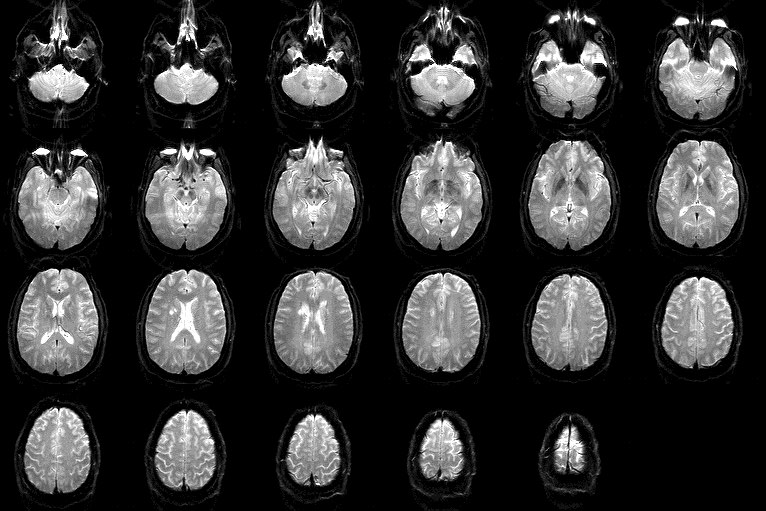

See the brainiac

See the brainiac ][